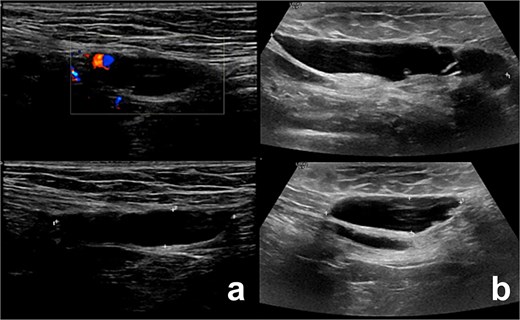

A 28-year-old woman presented with a 6-week history of a progressively enlarging, painful right groin lump. Examination revealed a small, mobile lump in the right inguinal region without erythema or tenderness. Ultrasound showed a 3 × 1.8 cm septated cystic lesion in the inguinal canal, with no hernia. Aspiration reduced its size to 1.8 × 0.9 cm with slight symptom relief, but the lesion recurred, enlarging to 3.5 × 1.0 cm after 2 weeks, causing radiating pain to the medial thigh. Follow-up ultrasound showed recurrence (Fig. 1a), prompting surgical exploration.

Illustrates the ultrasound findings for the two patients, highlighting the presence of the canal of Nuck cyst (case 1: a, case 2: b).

Ultrasound showed a 2.5 × 1.1 × 3.5 cm cystic lesion, without soft tissue components, located superficially and medial to the pubic bone at the level of the superficial inguinal ring. There was no communication with the peritoneum. These findings, as shown in Fig. 1b, were suggestive of a canal of Nuck cyst.